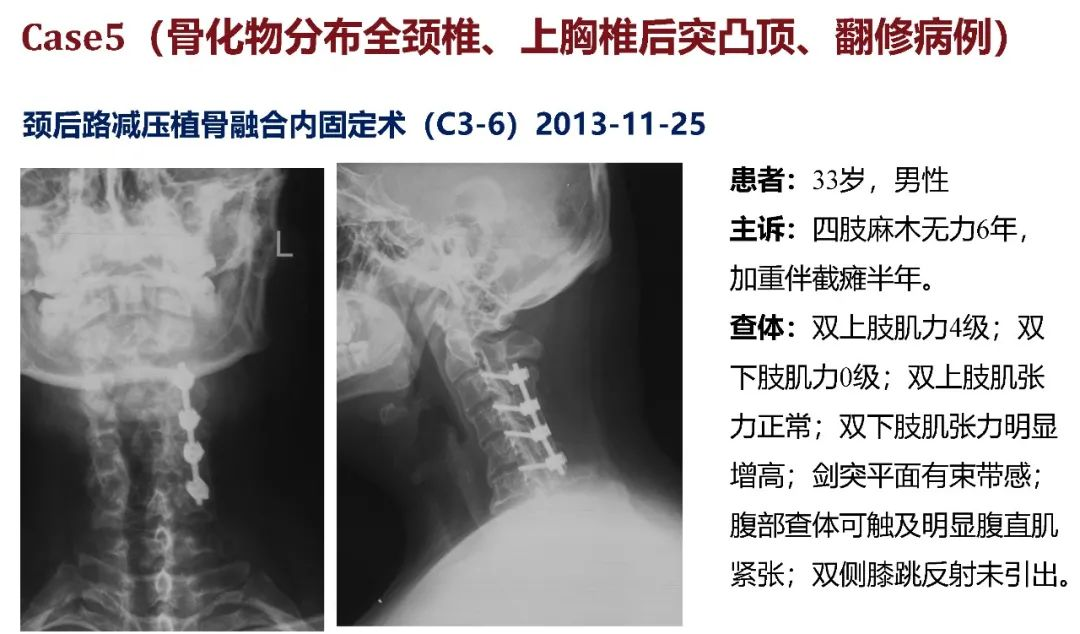

病史:M, 34 y/o

Present History:

Numbness of right lower limb for 2 months, weakness for 1 week

Urination disorder

Body Weight: 120Kg; BMI: 39.5